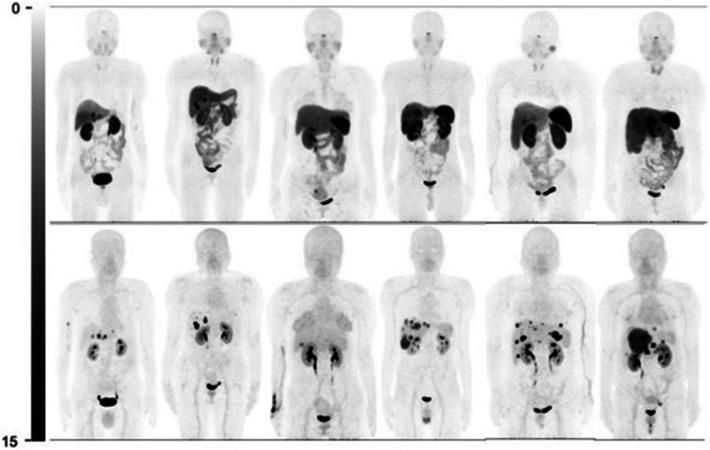

Neuroendocrine tumors (NETs) are a heterogeneous group of neoplasms characterized by their overexpression of somatostatin receptors (SSTRs), which can be utilized for peptide receptor radionuclide therapy. This review provides a comprehensive update on the clinical trials of radiolabeled SSTR-targeting radiopharmaceuticals since 2020, with a focus on somatostatin receptor agonists and antagonists radiolabeled with Ga, F, Tc, Lu, Tb, Pb, Cu, and Ac. Head-to-head clinical trials demonstrate that radiolabeled SSTR antagonists such as [Ga]Ga-DOTA-JR11 and [Ga]Ga-DOTA-LM3 offer improved lesion detection and tumor-to-background ratios (particularly in liver metastases) compared to radiolabeled agonists like [Ga]Ga-DOTA-TOC and [Cu]Cu-DOTA-TATE. Additionally, F-labeled agents offer logistical and dosimetric advantages over Ga, due to F's longer half-life and cyclotron production, allowing for delayed imaging and increased availability to a wider range of patients. Emerging targeted alpha therapy agents, including [Ac]Ac-DOTA-TATE, show promising results in treating disease resistant to conventional therapies due to the high linear energy transfer of alpha particles, which leads to improved localized cytotoxicity. Collectively, these developments support a shift toward more precise, receptor-specific theragnostics, emphasizing the need for further head-to-head clinical trials and integration of dosimetry-driven, personalized treatment planning in the management of NETs.

神经内分泌肿瘤(NETs)是一组异质性肿瘤,其特征在于生长抑素受体(SSTRs)的过度表达,可用于肽受体放射性核素治疗。本综述全面更新了自2020年以来放射性标记的靶向SSTR放射性药物的临床试验情况,重点关注用镓(Ga)、氟(F)、锝(Tc)、镥(Lu)、铽(Tb)、铅(Pb)、铜(Cu)和锕(Ac)标记的生长抑素受体激动剂和拮抗剂。头对头临床试验表明,与[Ga]Ga-DOTA-TOC和[Cu]Cu-DOTA-TATE等放射性标记激动剂相比,[Ga]Ga-DOTA-JR11和[Ga]Ga-DOTA-LM3等放射性标记SSTR拮抗剂在病变检测和肿瘤与背景比值方面表现更佳(尤其是在肝转移瘤中)。此外,由于F的半衰期更长且可通过回旋加速器生产,F标记的药物在后勤和剂量学方面比Ga具有优势,这使得可以进行延迟成像并让更多患者能够使用。新兴的靶向α治疗药物,包括[Ac]Ac-DOTA-TATE,由于α粒子的高线性能量传递导致局部细胞毒性增强,在治疗对传统疗法耐药的疾病方面显示出有前景的结果。总体而言,这些进展支持向更精确、受体特异性的诊疗方法转变,强调在NETs管理中需要进一步进行头对头临床试验以及整合剂量学驱动的个性化治疗方案。